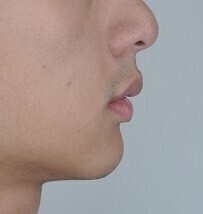

2. 돌출입교정

8. 비수술무턱교정